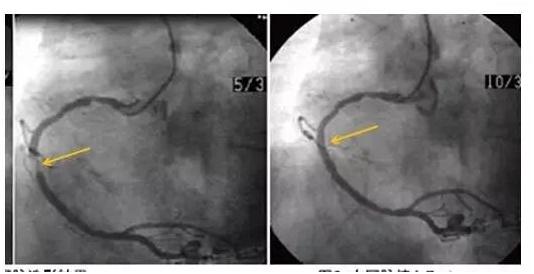

让我们深入探讨一下支架再狭窄的最新进展,科学家们正致力于研发一种新型的生物可降解支架,这种支架采用先进的生物材料制成,能够在完成血管疏通后自然降解,从而大大降低再次狭窄的风险,这种新型支架已经完成了初步的临床试验,结果显示其安全性和有效性都得到了验证。

让我们分享一个真实的案例,一位患者成功接受了新型生物可降解支架的治疗,术后恢复良好,再也没有受到支架再狭窄的困扰,他的生活重新回到了正轨,可以继续享受生活的美好,这样的案例给我们带来了希望和信心,让我们相信医学的进步可以带来更好的生活。